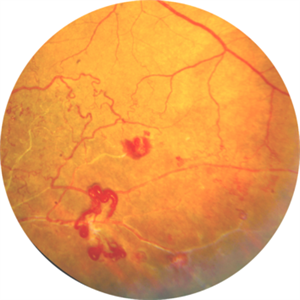

Cheese Pizza Pie Appearance in CMV Retinitis

This is Fundus Photograph of left eye of 53 year male depicting an area of Retinal Necrosis with few Retinal Haemorrhages suggestive of CMV Retinitis. Areas of Perivascular Exudation also seen. On investigations, the patient was found to be HIV positive. He was started on Anti Retro Viral treatment after physician opinion.

Photographer: Dr. Kanwaljeet Harjot Madan, Thind Eye Hospital, Jalandhar City (Punjab) INDIA.

Imaging device: Zeiss Fundus Camera

Condition/keywords: AIDS, cytomegalovirus (CMV), retinitis